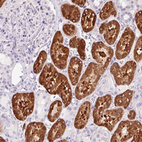

Immunohistochemistry analysis in human liver and colon tissues using HPA036114 antibody. Corresponding FTCD RNA-seq data are presented for the same tissues.